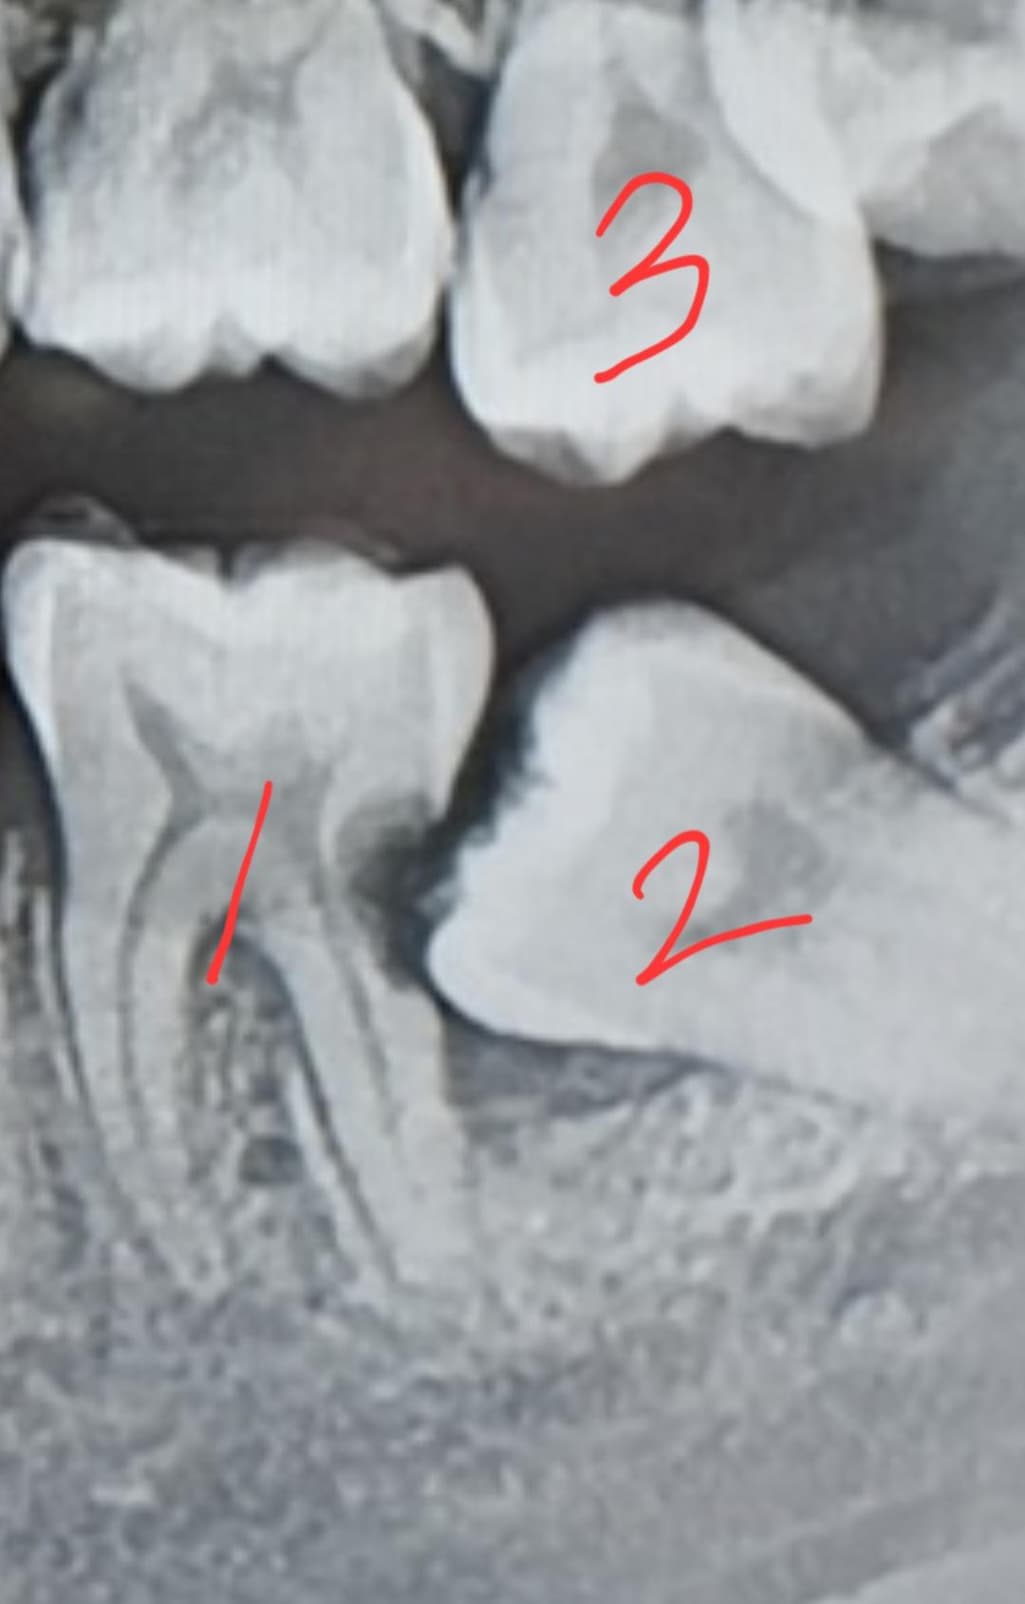

사진 속 아랫니는 둘 다 어금니 입니다...씹을 때 가장 중요하다는 두 치아가 모두 저 모양이죠...

치과에서 말하는 방법은 대부분 2번 치아 발치, 1번 치아 크라운, 3번 치아 크라운, 그리고 후에 2번 치아 자리에 임플란트입니다.

그런데 최근 가장 유명하고 규모가 큰 병원에 가보니, 1번 치아도 발치하고 임플란트를 권하더군요. 충치가 옆에 생겼기 때문에, 크라운을 해도 정말 몇일만에 못 쓸 수도 있을 것 같으니 임플란트가 맞는 것 같다고요.

사진에 보이는 1.2번 치아는 발치를 하시고 나서 임플란트를 하시는게 좋을것같습니다. 사랑니 떄문에 앞치아가 많이 썩어서 발치를 하셔야될것같습니다.

사랑니는 기울어져 있고 앞에 치아의 충치를 유발할 수 있기 때문에 발치를 해야 되는 것이 맞습니다. 하지만 사랑니 앞에 있는 치아는 충치를 치료하고 신경치료를 하고 나면 충분히 사용을 할 수 있습니다. 가능하면 자신의 치아는 뽑지 않고 치료를 해서 사용할 수 있도록 하는 것이 좋습니다.

임플란트가 필요할 것 같습니다. 치아가 누우면서 해당 치아의 뿌리가 너무 약해졌습니다.